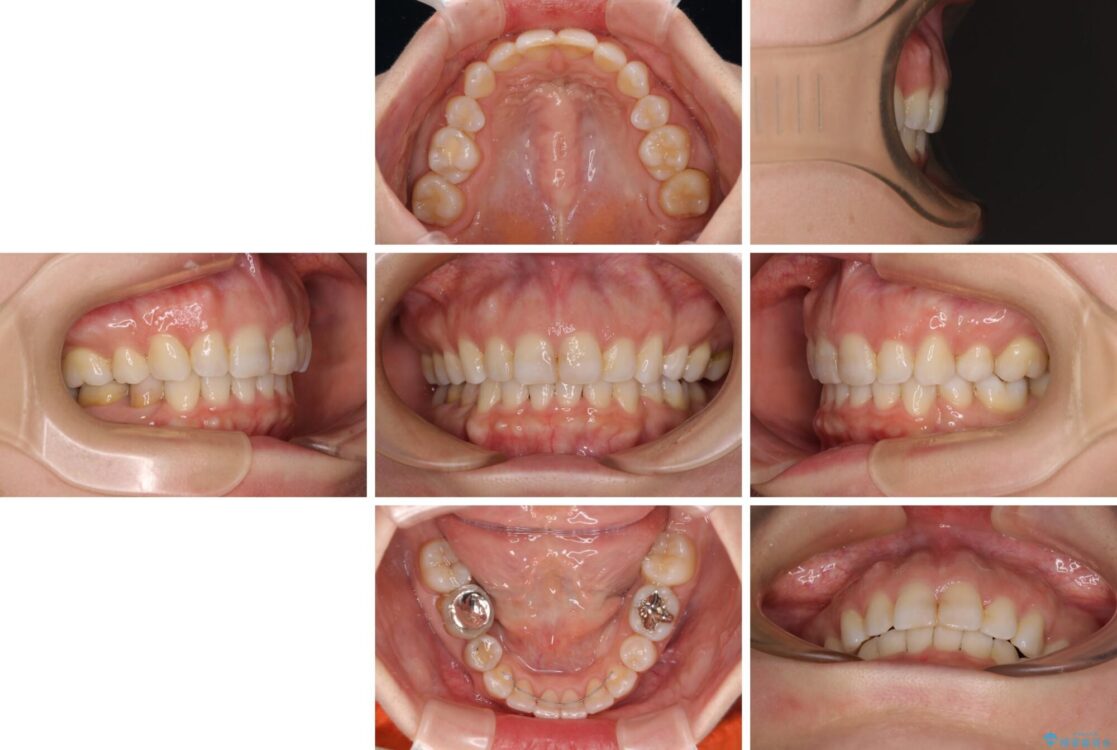

治療後

• 【モニター】出っ歯と咬み合わせを改善 ワイヤー装置の抜歯矯正 治療後画像

治療後について

奥歯の咬み合わせ改善には1年ほどの期間と処置中の噛みにくさを強いることとなりましたが、抜歯後はスムーズに治療を完了させることができました。

歯ぎしりの際に奥歯が干渉していた咬み合わせも理想的な状態に改善できました。